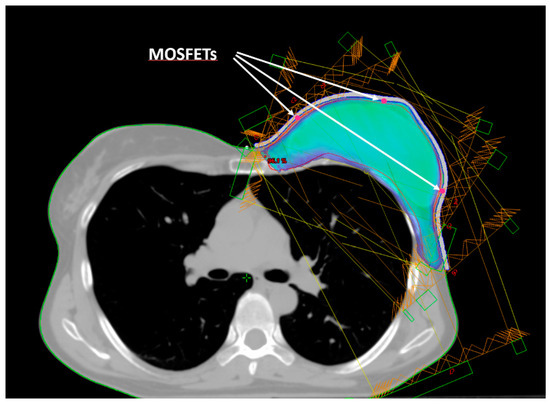

Five small spherical ROIs were freehand-contoured onto the patients’ CTs at the skin–bolus interface at the positions where the dose was planned to be evaluated. The five ROIs were subtracted from the bolus ROI, generating five holes at its inner surface, which served as suitable housings for the positioned MOSFET dosimeters (Figure 2). Thus, for the following dosimetric evaluation, the position of the MOSFETs at the bolus inner surface corresponded to the ROIs contoured on the TPS. Figure 1 shows the five chosen positions: A—cranial; B—central; C—caudal; D—medial; and E—external.

Figure 2. Beam arrangement for IMRT dose delivery. Isodose of 95% of the prescribed dose. The arrows indicate the positions (red dots) of the three mid-height MOSFETs (E, B, D).